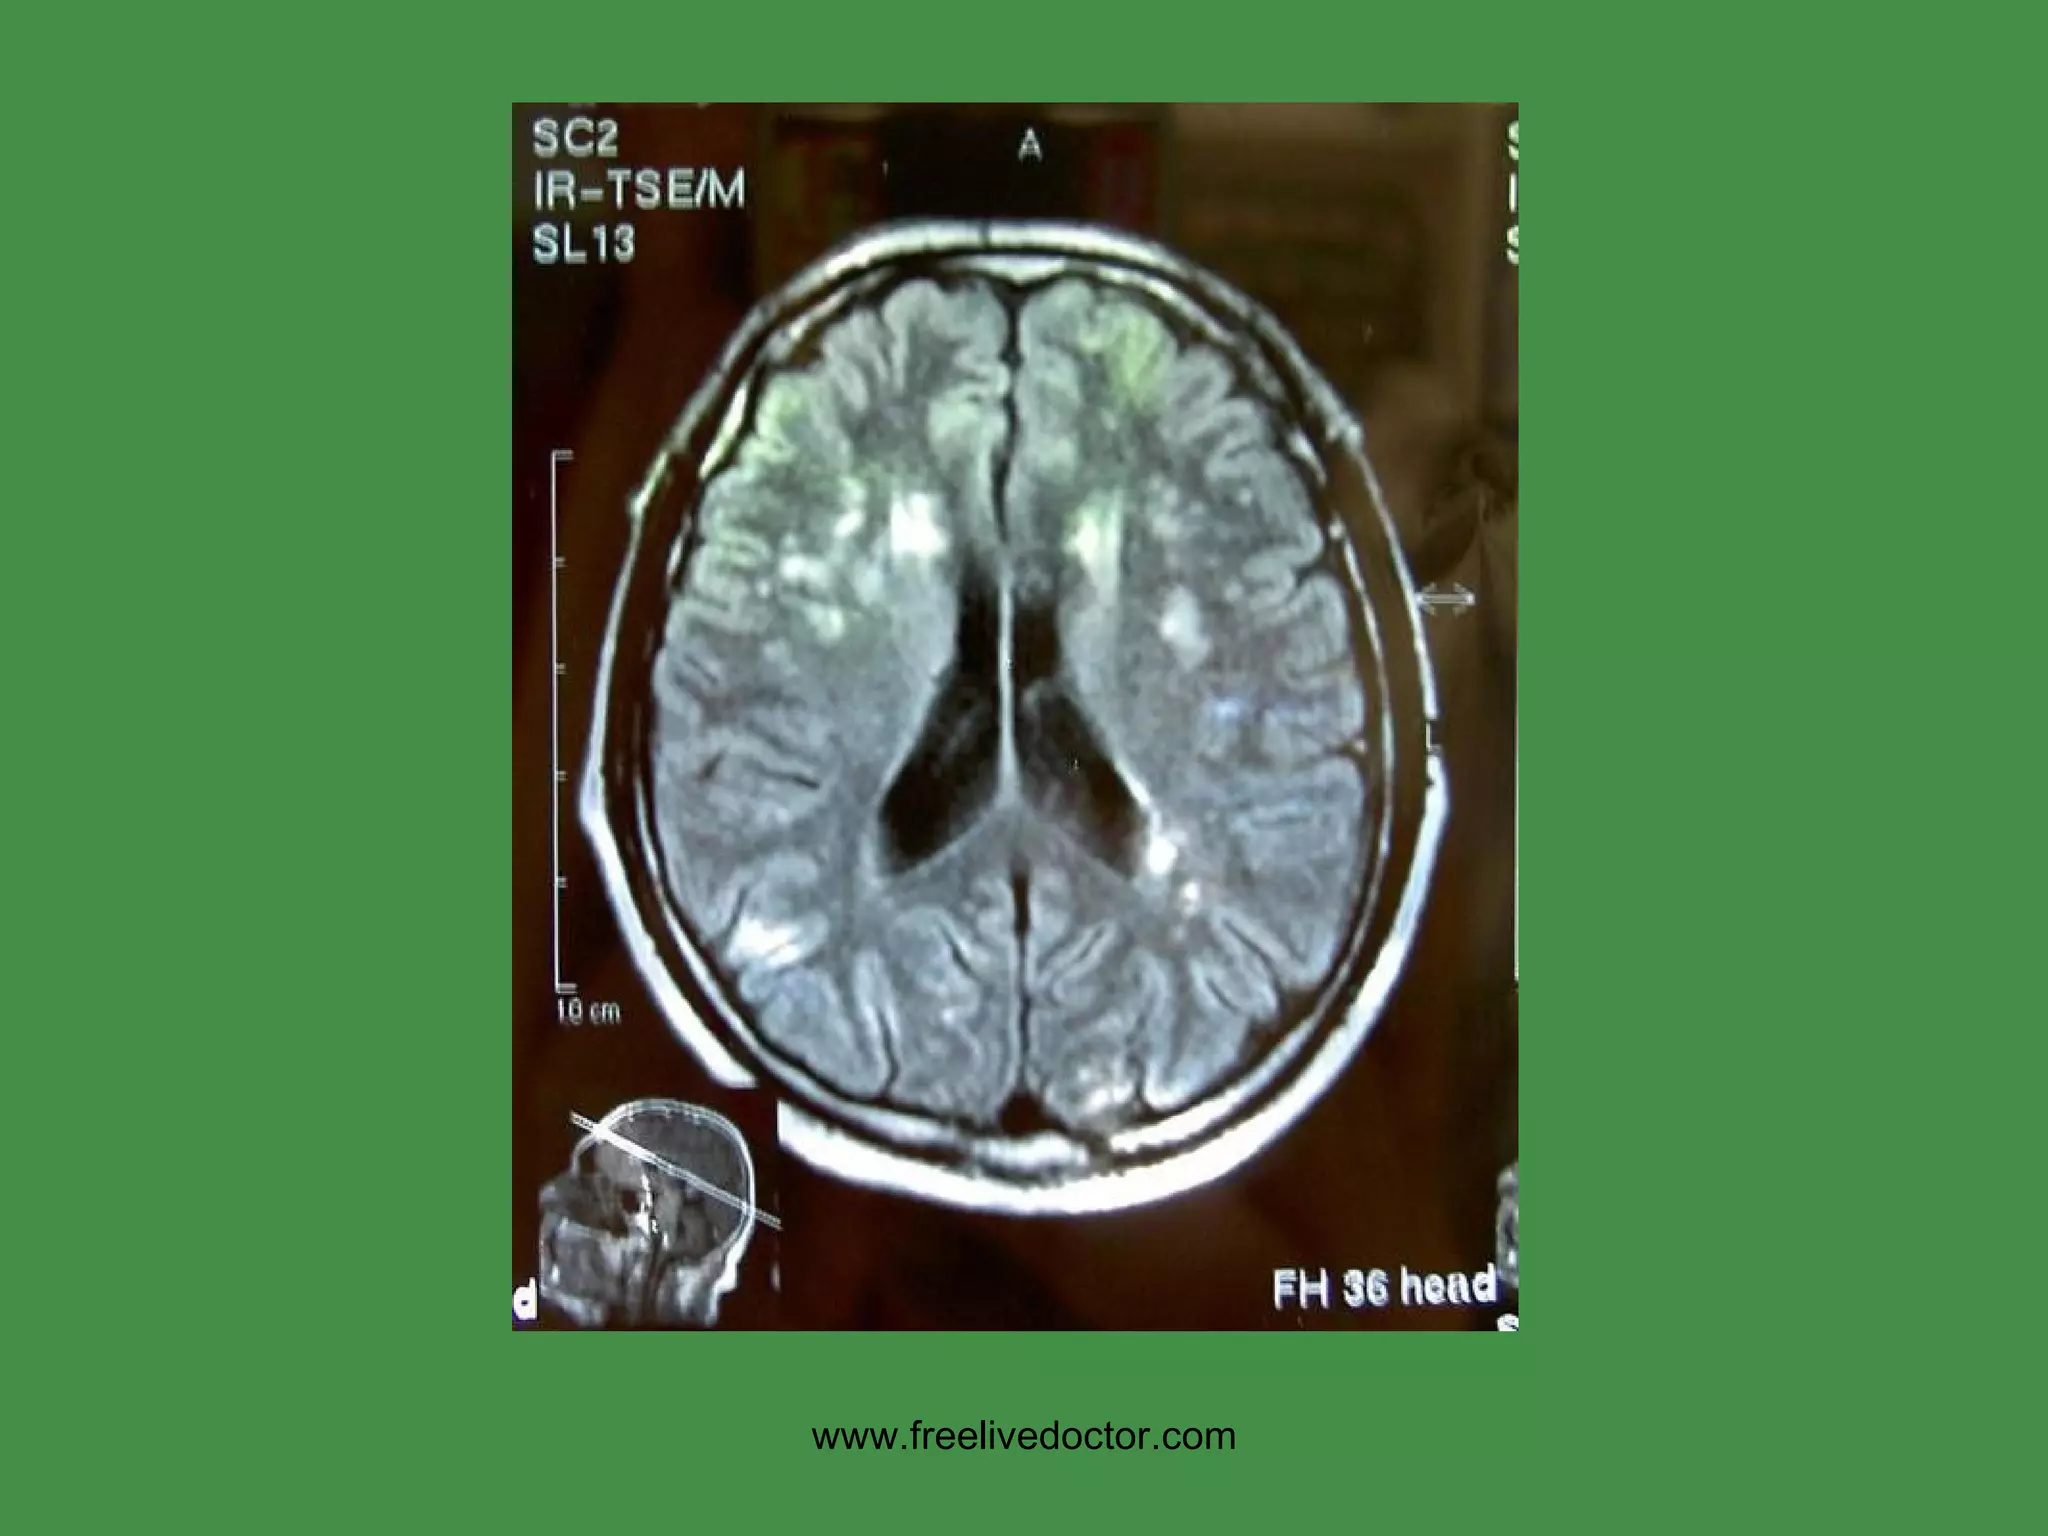

MS Cause:  ? USA prevalence:  1:1000  F>>M,  Ages: 30’s, 40’s Immune response primarily against CNS myelin (white matter) Regional area of white matter demyelination is called “PLAQUE” Increased CSF gamma globulin, i.e., oligoclonal bands Often presents with VISUAL problems EXACERBATIONS/REMISSIONS www.freelivedoctor.com

• #91 Demyelination is associated with gliosis and edema, therefore bright signals on T2 weighted images

• #105 Demyelination, generically, is a NON-specific pattern of CNS reaction to injury of many types and usually goes hand in hand with edema and gliosis, If it wasn’t for the “edema” associated with demyelination, the “plaques” would not be seen on MRI.

• #107 MS gave MRI its first HUGE boom, by virtue of being able to detect these lesions, due to edema!